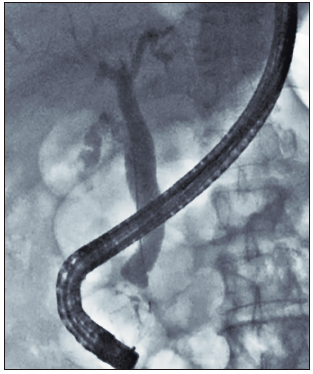

Por la edad del paciente, el hallazgo de los DDP y la dilatación del conducto pancreático principal, se decidió complementar el estudio diagnóstico con la realización de una ultrasonografía endoscópica (USE) biliopancreática, para descartar la presencia de neoplasias pancreatobiliares no evidenciadas en los estudios previos de imágenes. La USE biliopancreática mostró la presencia de un DDP de gran tamaño, dilatación coledociana y escaso barro en la vesícula biliar. El páncreas no presentaba alteraciones y el conducto pancreático principal no se encontraba dilatado. Con los hallazgos descritos, se descartó la presencia de coledocolitiasis y neoplasias pancreatobiliares, y se postuló como hipótesis diagnóstica el síndrome de Lemmel. El tratamiento elegido fue la realización de CPRE más esfinterotomía biliar, dada su baja tasa de morbimortalidad y la alta probabilidad de éxito, sobre la base de los reportes de casos previos. El paciente fue sometido a una nueva CPRE, en la cual se retiró la prótesis biliar (Figuras 4 y 5). La colangiografía mostró dilatación del colédoco (Figura 6), sin evidencia de litiasis. Se realizó el pasaje del balón extractor de vía biliar sin evidenciarse salida de litos ni barro biliar al retirarse este. Posteriormente, se amplió el acceso a la vía biliar mediante esfinterotomía, siendo adecuados el drenaje de bilis y el contraste. El hallazgo de barro en la vesícula biliar fue resuelto mediante colecistectomía laparoscópica. El paciente fue dado de alta sin molestias y el control de la analítica sanguínea fue normal. Tras seis meses de seguimiento, el paciente aún permanece asintomático.

Figura 6. Colangiografía que muestra dilatación del conducto biliar común, sin

evidencia de imágenes, por defecto del relleno.